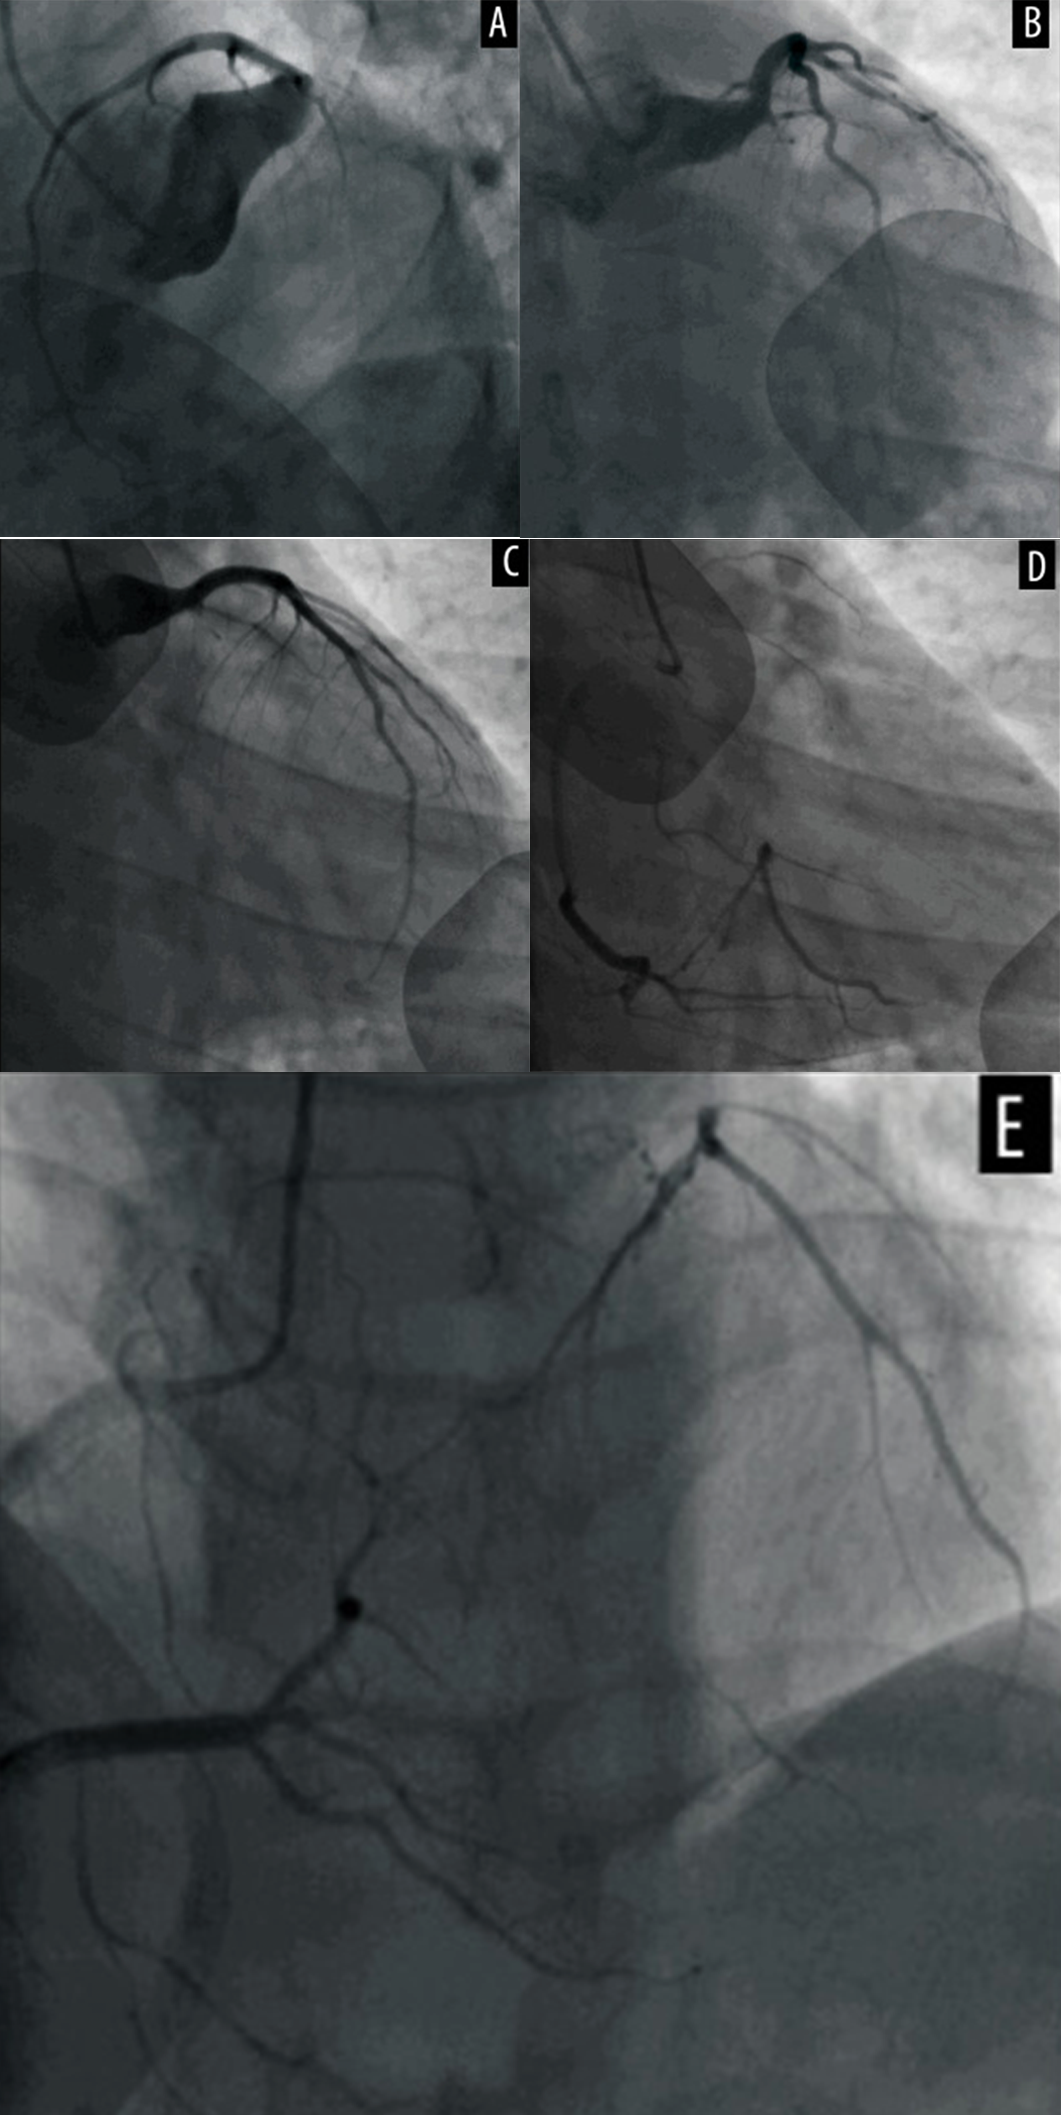

冠脉扩张症定义为弥漫性扩张累及范围超过其长度的1/3以上,且扩张段的直径是相邻正常段直径的1.5倍以上。这与冠脉瘤的定义不同,后者是指冠脉某段直径超过相邻正常冠脉段直径的1.5倍,且累及范围占总长度的1/3以下。冠脉扩张症有时会导致急性冠脉综合征。研究显示,扩张段存在明显的血流缓慢现象,可能导致缺血和血栓形成。近期,天津医大总医院李永乐教授团队在《American Journal of Case Reports》报道了一份特殊病例“Recurrent Acute Myocardial Infarction in a Patient with Severe Coronary Artery Ectasia Followed Up for 10 Years: Implications of Anticoagulant Therapy”,报告了一例在9年间因同一冠脉扩张病变部位局部血栓形成导致再发心肌梗死的病例,并讨论了长期抗凝治疗的有效性。

对于急性心肌梗死合并严重冠脉扩张的患者,局部血流瘀滞会导致局部血栓形成。对于这类患者,应考虑终身抗凝治疗作为预防措施,而新型口服抗凝药可能是有效预防血栓形成的更好选择。